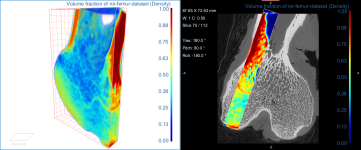

This section of the tutorial describes how to use the Bone Analysis module for 3D volume fraction plotting. You should note that volume fractions are scalar maps.

Comparison of volume fraction scalar map (on left) with vector-based field of anisotropy (on right)

The images below (from left to right) correspond to XZ, XY, and oblique orientations. The computed vector fields are colored by magnitude.

High-definition vector field-based surface anisotropy maps